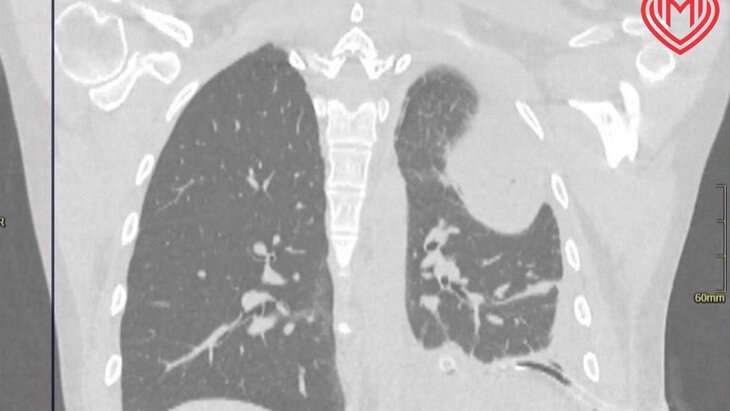

По итогам обследования медики диагностировали женщине редкую патологию – парахиатальную грыжу. В образовавшееся отверстие диафрагмы пациентки попала большая часть желудка, которая перестала кровоснабжаться и погибла.